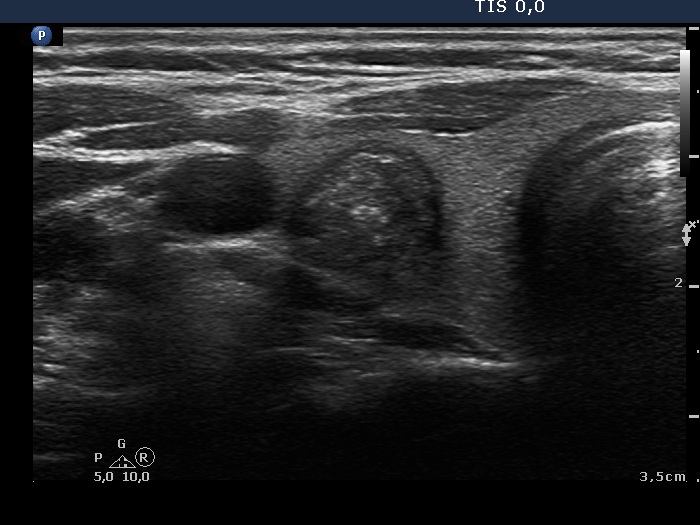

Papillary carcinoma (histological diagnosis) |

This case is less edifying or may be more edifying. Compared with the previous case, the granules here are less bright. Nevertheless, great proportion of them belong to punctate echogenic foci (arrows). It is worth to compare these with non-specific granules (arrowheads). |